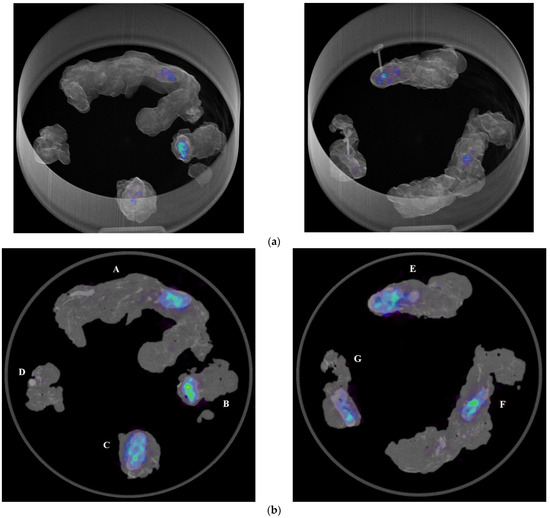

3. Results

In the operating room, the acquisition of the specimens 68Ga-PSMA-11 PET/CT images with the intraoperative PET/CT scanner proved to be safe and feasible. The median time between radiotracer injection and specimen PET/CT imaging of the pelvic lymph nodes was 125 min. On average, the time required to complete the scanning process of a specimen case was 12 min. Figure 1a,b show the volume rendering of the PET/CT acquisitions, as well as two sample axial slices denoting mild tracer uptake in nodal structures.

Figure 1. (a) Volumetric rendering and axial view (b) of 68Ga-PSMA-11 PET/CT specimen images of the pelvic lymph nodes of a high-risk prostate cancer patient undergoing robot-assisted radical prostatectomy (RARP) and pelvic lymph node dissection (PLND). A, B: left obturator, C: left proximal external iliac, D: left distal external iliac, E: right distal external iliac, F: right obturator, G: right proximal external iliac.

Diagnostics 13 03013 g001